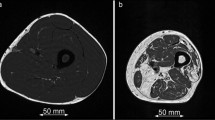

The calves of seven healthy subjects underwent imaging pre- and post-exercise via 7 T 23Na MRI (3D fast low angle shot, TR/TE = 80 ms/0.160 ms, 4 mm × 4 mm × 4 mm) and 1 week later by 1H MRI (multiple spin-echo sequence, TR/TE = 3,000 ms/15–90 ms). Four type 2 diabetics also participated in the 23Na MRI protocol. Pre- and post-exercise sodium signal intensity (SI) and proton T2 relaxation values were measured/calculated for soleus (S), gastrocnemius (G), and a control, tibialis anterior (TA). Two-tailed t tests were performed.

In S/G in healthy subjects post-exercise, sodium SI increased 8–13% (p < 0.03), then decreased (t 1/2 = 22 min), and 1H T2 values increased 12–17% (p < 0.03), then decreased (t 1/2 = 12–15 min). In TA, no significant changes in sodium SI or 1H T2 values were seen (−2.4 to 1%, p > 0.17). In S/G in diabetics, sodium SI increased 10–11% (p < 0.04), then decreased (t 1/2 = 27–37 min) without significant change in the TA SI (−3.6%, p = 0.066).